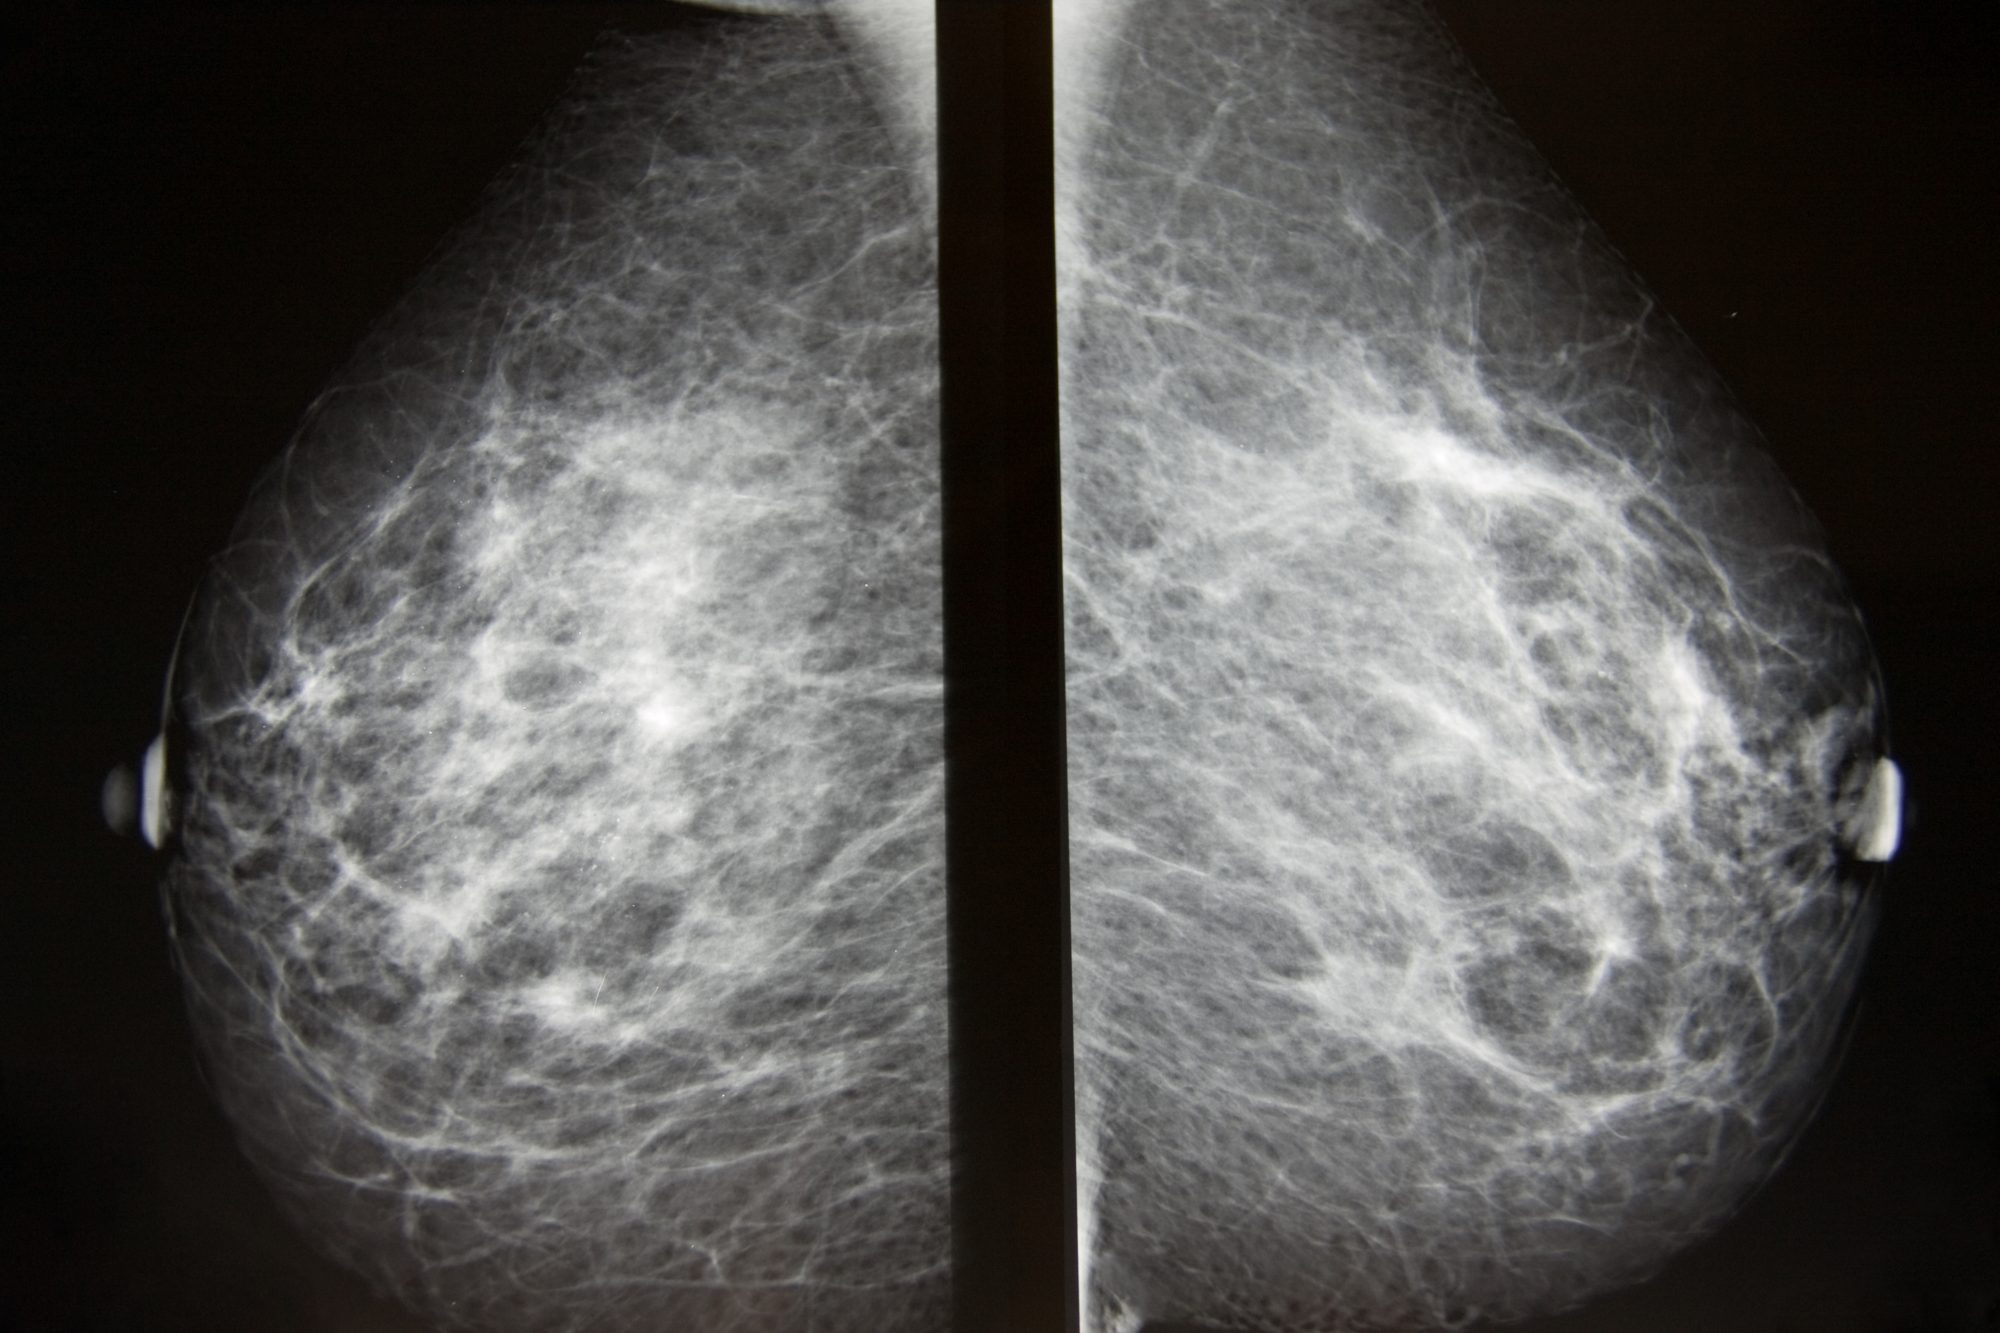

Аномалии молочной железы: медицинские примеры и визуализация

Раздел: Мудрость в деталях